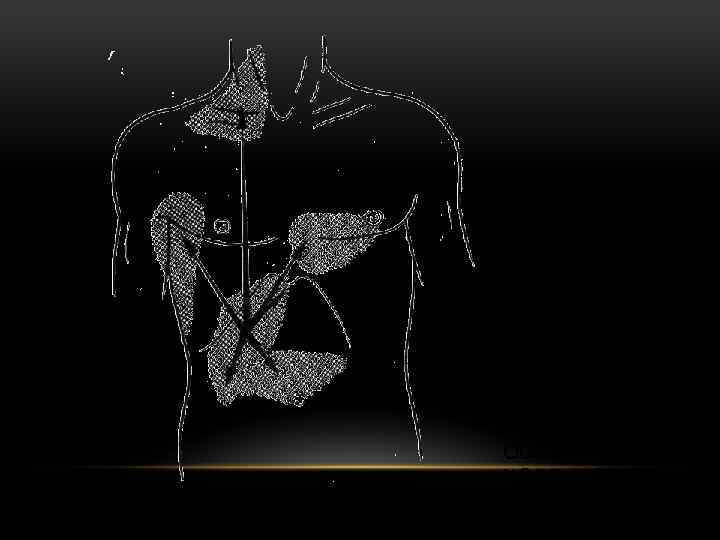

ВОЗМОЖНАЯ ИРРАДИАЦИЯ БОЛИ ПРИ ОСТРОМ ХОЛЕЦИСТИТЕ.

ВОЗМОЖНАЯ ИРРАДИАЦИЯ БОЛИ ПРИ ОСТРОМ ХОЛЕЦИСТИТЕ.